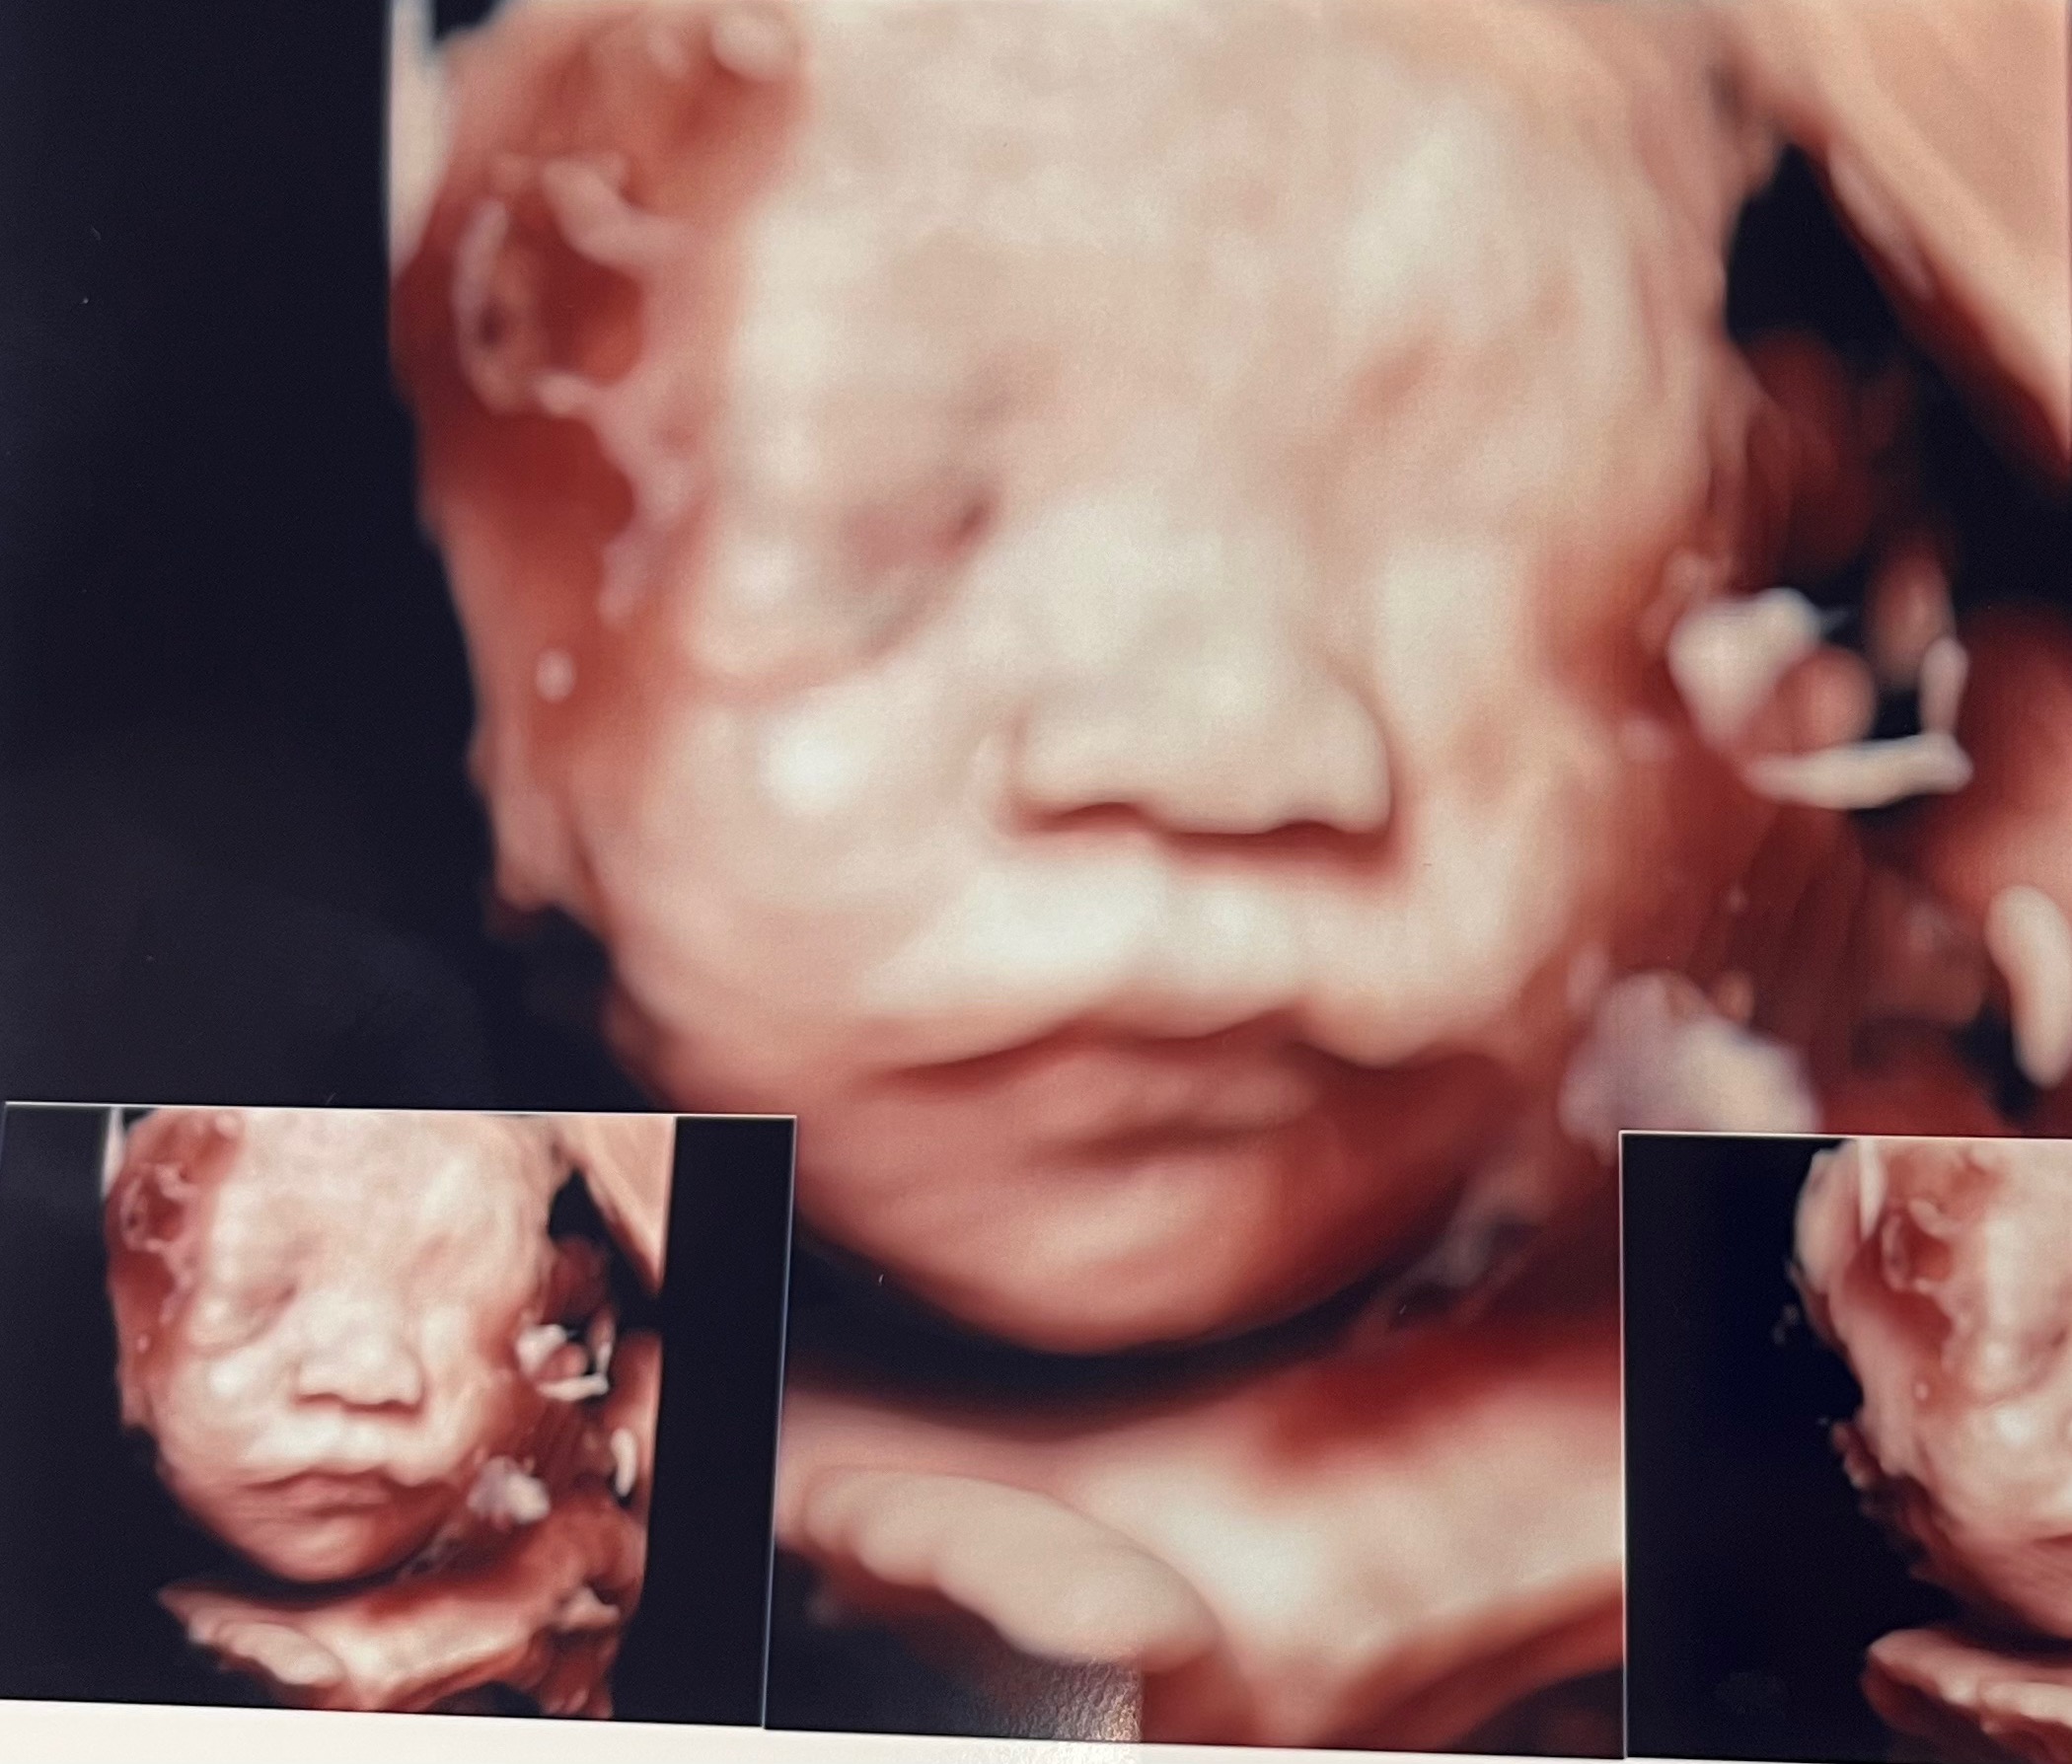

[28주] 입체초음파 한번에 성공 후기 (+ 베이비페이스)

한국에 방문한 시기가 26-28주차였어요. 제가 미국에서 머물면서 임신을 하게되어 울엄마의 첫딸내미 (나) 임신에 대한 추억이 전혀 없으신게 아쉽더라구요, 그래서 손녀딸 입체초음파를 한번 같이 가볼까 싶어서 한국서 다니던 산부인과를 방문했습니다. 제가 다니던 병원은 입체초음파의 경우 **장스여성병원** 28주 이후는 입체 초음파의 효과를 보장할 수 없다고 미리 예약할때부터 안내를 해주더라구요. (저희 병원 추천은 26-28주차라고 합니다) 이건 병원마다 매우 다른거같았어요 (검색결과 대부분 26-30주차사이이긴 한듯해요) 한번의 기회밖에 없는 과연 한번에 성공할 수 있을까 두근두근하는 마음이었는데요, 사실 너무 바쁜 스케쥴이라서 아무 준비도 못하고 갔습니다 @,@ 원래 그 전날 생각에는 초코우유라도 사서..